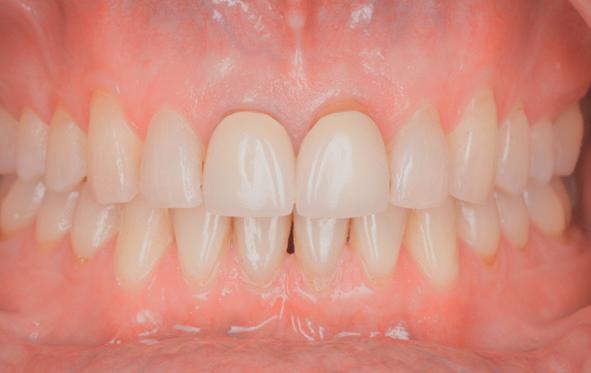

Esthetiek in de tandheelkunde, met name in het front, is een samenspel tussen de roze zachte weefsels en de witte harde weefsels. In het Engels wordt dit ook wel aangeduid met “pink and white esthetics”, waarbij het verkrijgen van correcte pink esthetics over het algemeen een grotere uitdaging vormt dan de white esthetics. Deze roze esthetiek is vooral van belang bij gebitselementen waarbij sprake is van recessie (het terugtrekken van de gingivalijn, waardoor de radix en een langere tand zichtbaar worden). De situatie wordt nog uitdagender wanneer een tand of kies niet is aangelegd, of in het verleden is verwijderd. Het element zorgt er immers voor dat de gingiva rondom de natuurlijke kroon ligt en dat er voldoende weefseldikte rondom deze kroon aanwezig is. Als het element ontbreekt, groeit het alveolaire bot dicht, omdat er geen radix meer is, en daarmee ook de mucosa (wanneer er geen element meer aanwezig is, spreken we niet meer van gingiva maar van mucosa), die dan afgevlakt is. De papillen tussen de afwezige elementen vlakken dan ook af.

Om één of meer afwezige elementen te herstellen bij een vaste voorziening, kan er een etsbrug of kunnen er implantaten worden geplaatst. De esthetiek valt of staat hierbij met de aanvulling van de zachte weefsels, zowel in de vorm van verbreding hiervan als het creëren van een zogenoemd emergence profile –dat wil zeggen dat de tand op een natuurlijk ogende wijze vanuit het tandvlees tevoorschijn moet komen.

tinaal geslepen te worden als er geen 1,5 mm ruimte voor de vleugels behaald kan worden. De ruimte was op de dunste plekken 1 mm, dus een kleine preparatie in de 12 en 22 palatinaal was nodig. Omdat de kaak volledig afgevlakt was en dun was geworden, kunnen de dummies van de etsbrug enkel op de kaak “gelegd worden”, maar daarbij zijn er geen papillen en staat de cervicale rand van de dummies net voor de kaak. Een esthetisch resultaat kan daarmee niet behaald worden. Daarom is een aanvulling van de zachte weefsels in de breedte nodig, als het creëren van een emergence profile, waarbij het oogst alsof de gebitselementen uit het weefsel vertrekken.

18. Etsbrug frontbeeld